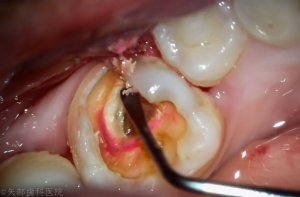

カリエスチェックで軟化象牙質の染め出しを行います。虫歯になっている部分が赤く染まります。

これにより軟化象牙質の徹底した除去が行えます。軟化象牙質をしっかり除去せずに根管治療を行っても症状が治らない場合があります。